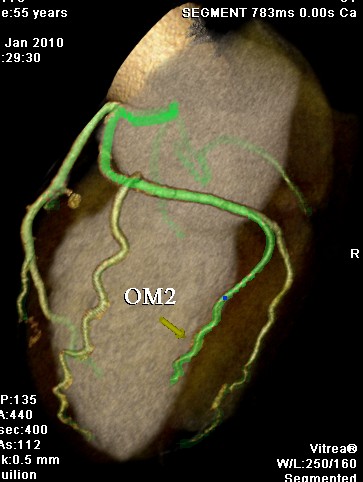

标题: CT24400:患者54岁,心前区不适进行心脏冠脉造影检查。 [打印本页]

标题: CT24400:患者54岁,心前区不适进行心脏冠脉造影检查。

患者54岁,心前区不适进行心脏冠脉造影检查。高手看看有问题没有?

图像很漂亮,好像未见异常